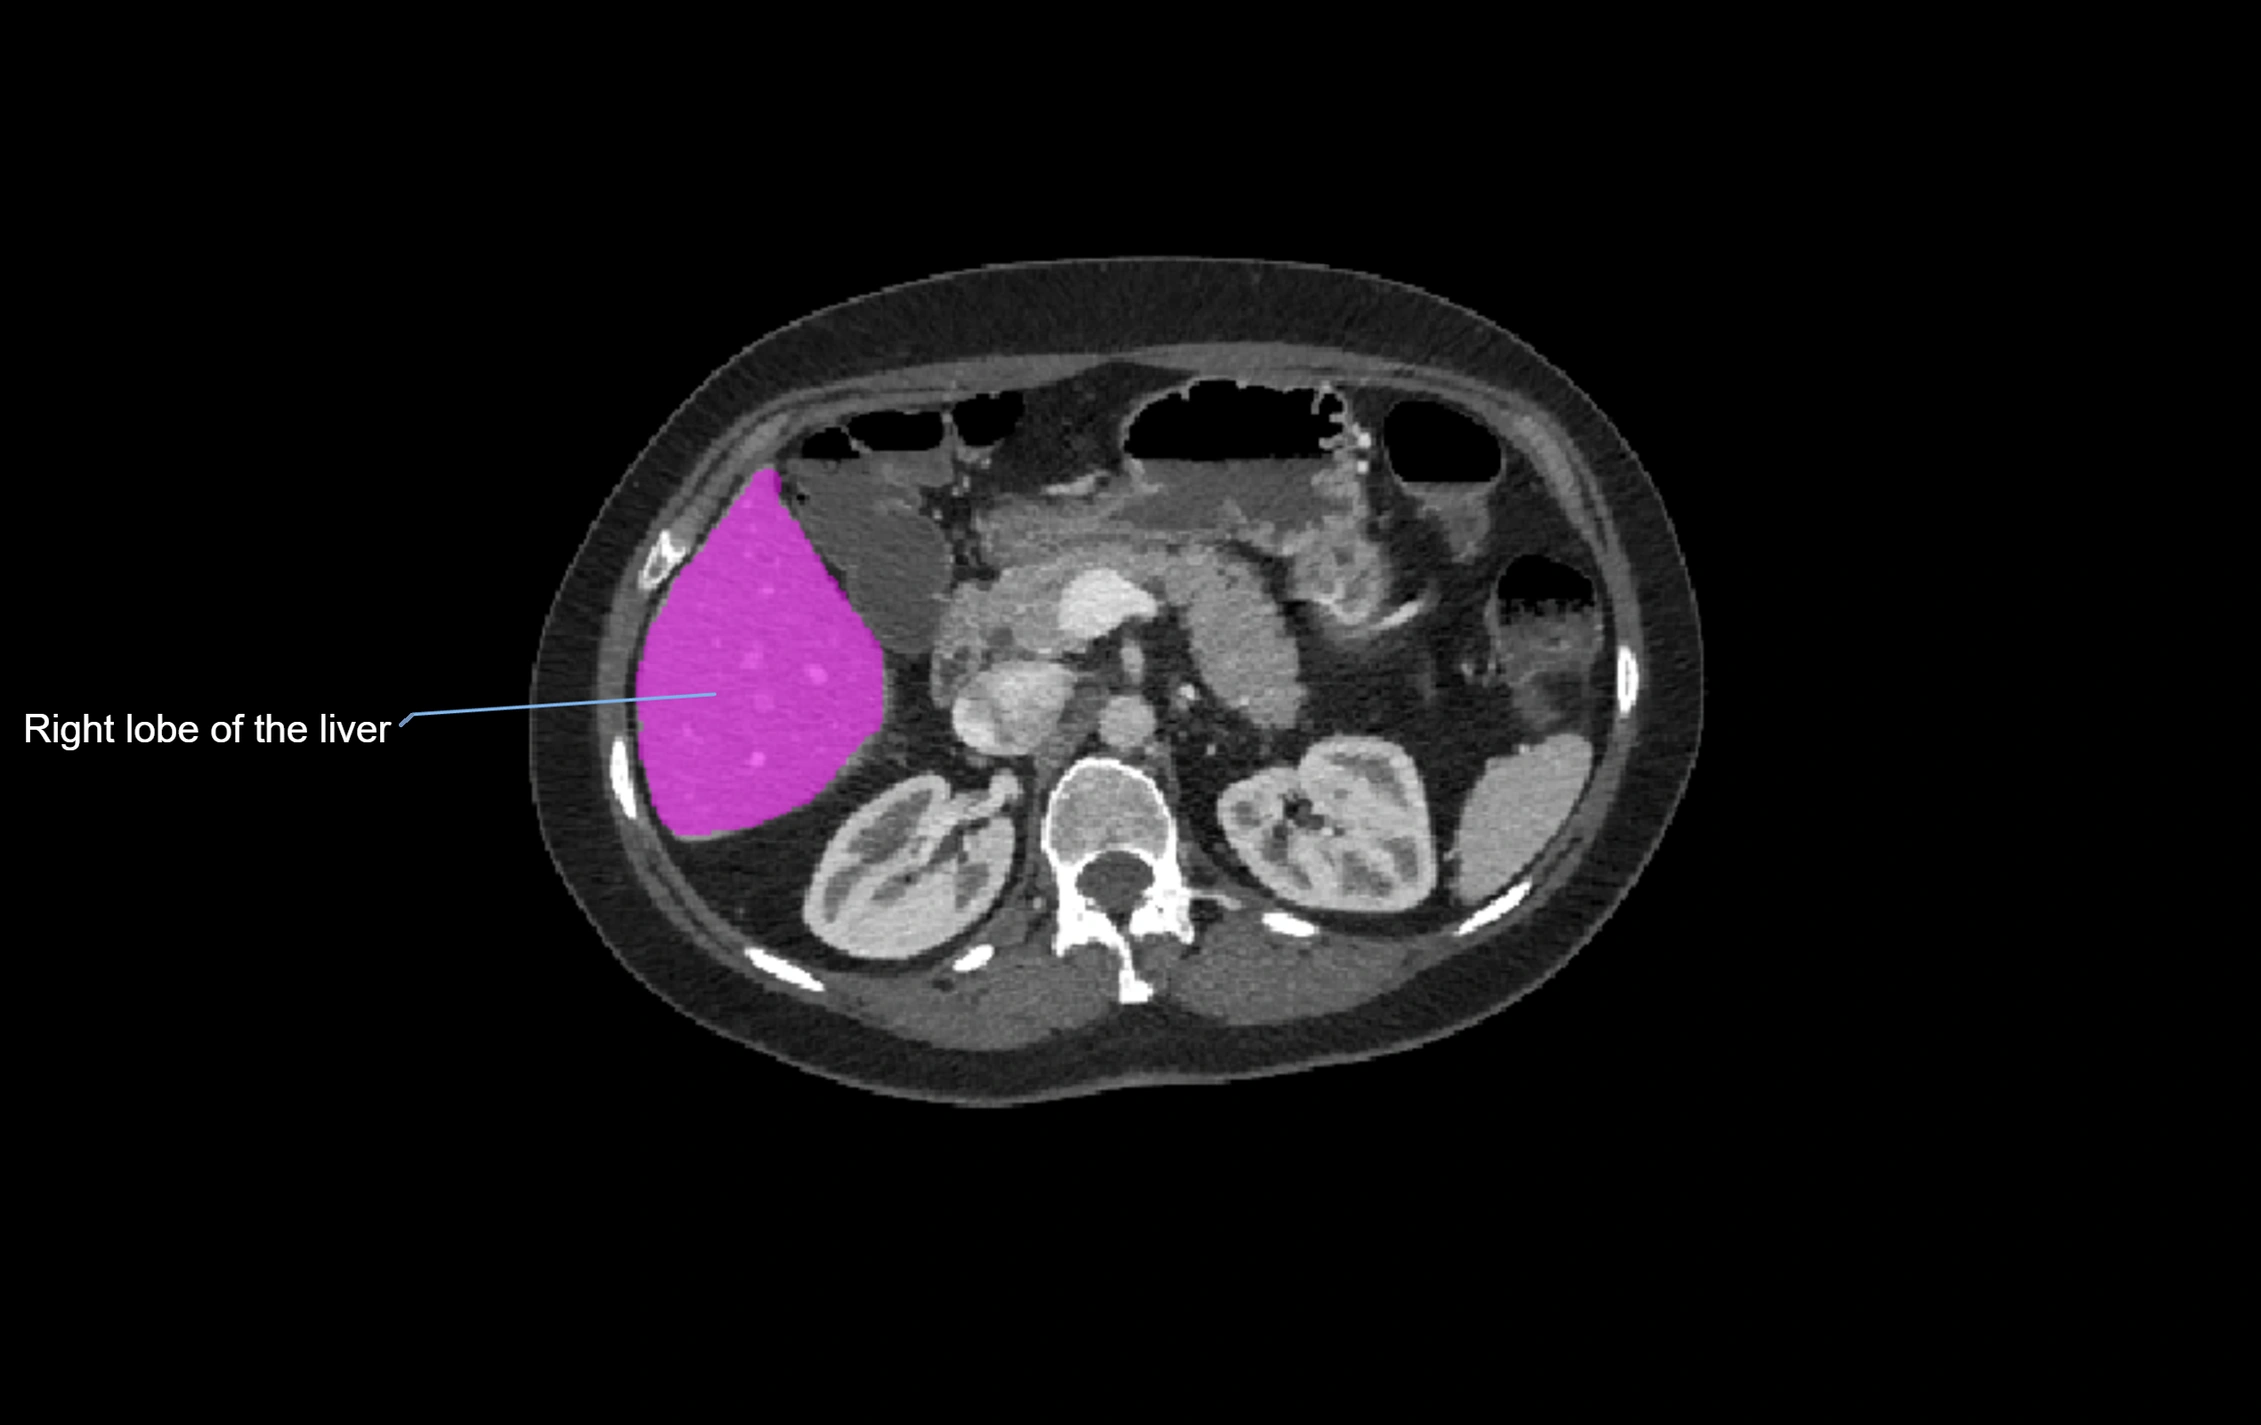

CT Image

image